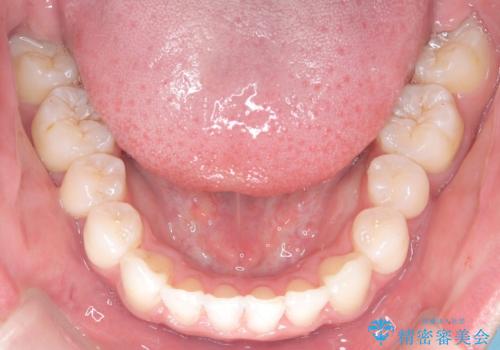

- 前歯が出ていることを主訴に来院されました。

臼歯関係が上顎前突傾向のため、上顎小臼歯を抜歯してインビザラインにて治療を行いました。

臼歯の咬合を作るために治療終盤ではゴムかけを行なっています。